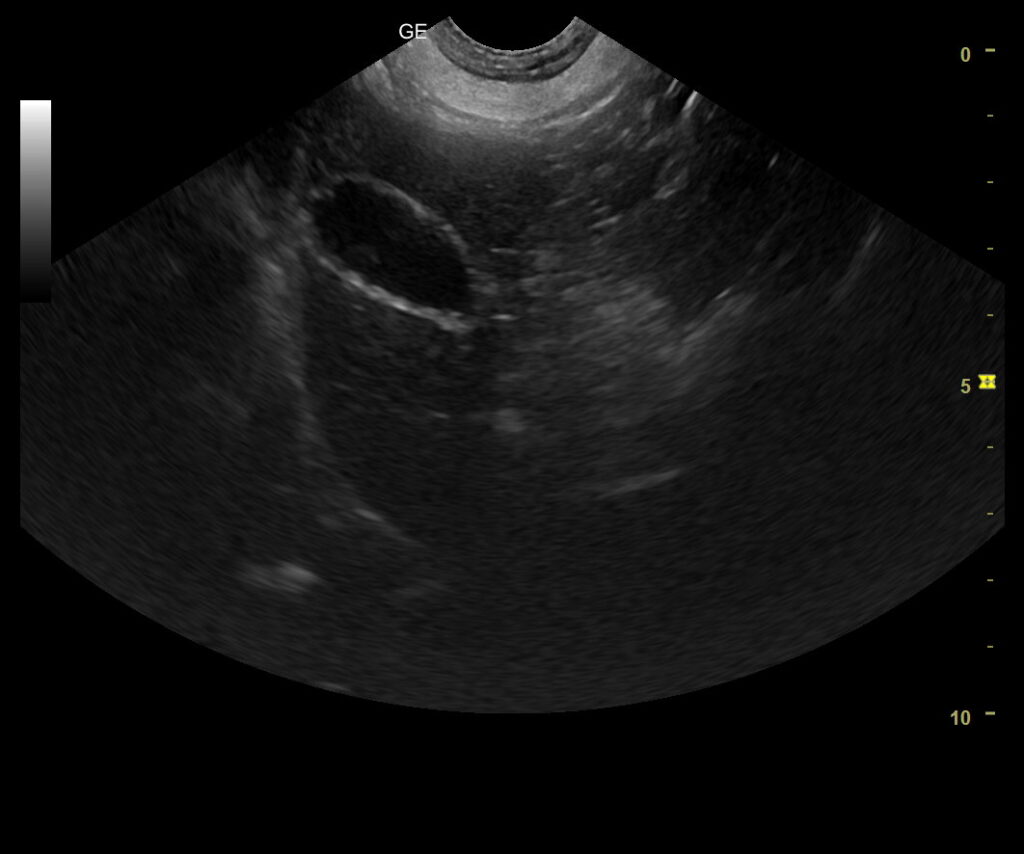

Til tross for vellykket operasjon fortsatte Dino å kaste opp. Nye blodprøver, ultralyd og avføringsprøver ble tatt. Det ble da oppdaget en forstørret prostata.

Benign prostatisk hyperplasi er en vanlig, hormonelt betinget forstørrelse av prostata hos eldre, ikke-kastrerte hannhunder. Tilstanden kan gi fordøyelsesproblemer, ubehag og i enkelte tilfeller påvirke allmenntilstanden.